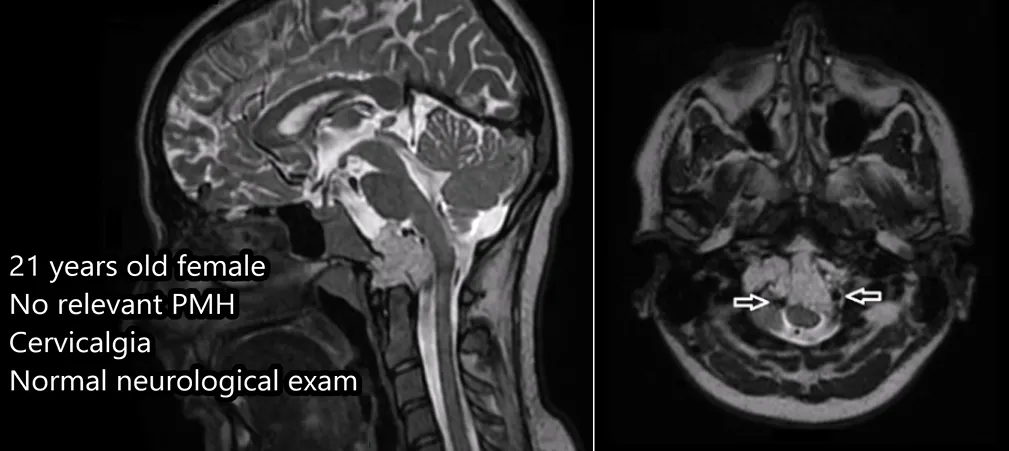

21岁女性-前外侧入路成功切除肿瘤

病情回顾:

21岁法国女孩,出现颈部疼痛,MRI检查显示肿瘤集中在枕骨大孔和颅颈交界区的内部,病变拓展至硬膜内,累及双侧椎动脉。该名脊索瘤患者还伴有明显的骨质损害和硬膜内延伸。

术前MRI

福教授为这名患者使用一种不太常见的颅颈交界区手术入路——前外侧入路。这种手术入路初期由福教授的导师伯纳德·乔治(Bernard George)阐述,当然福教授也证明了他对这一手术入路的熟练掌握及高超的手术技术。使用前外侧入路并以进入颅颈交界区,顺利地切除肿瘤。